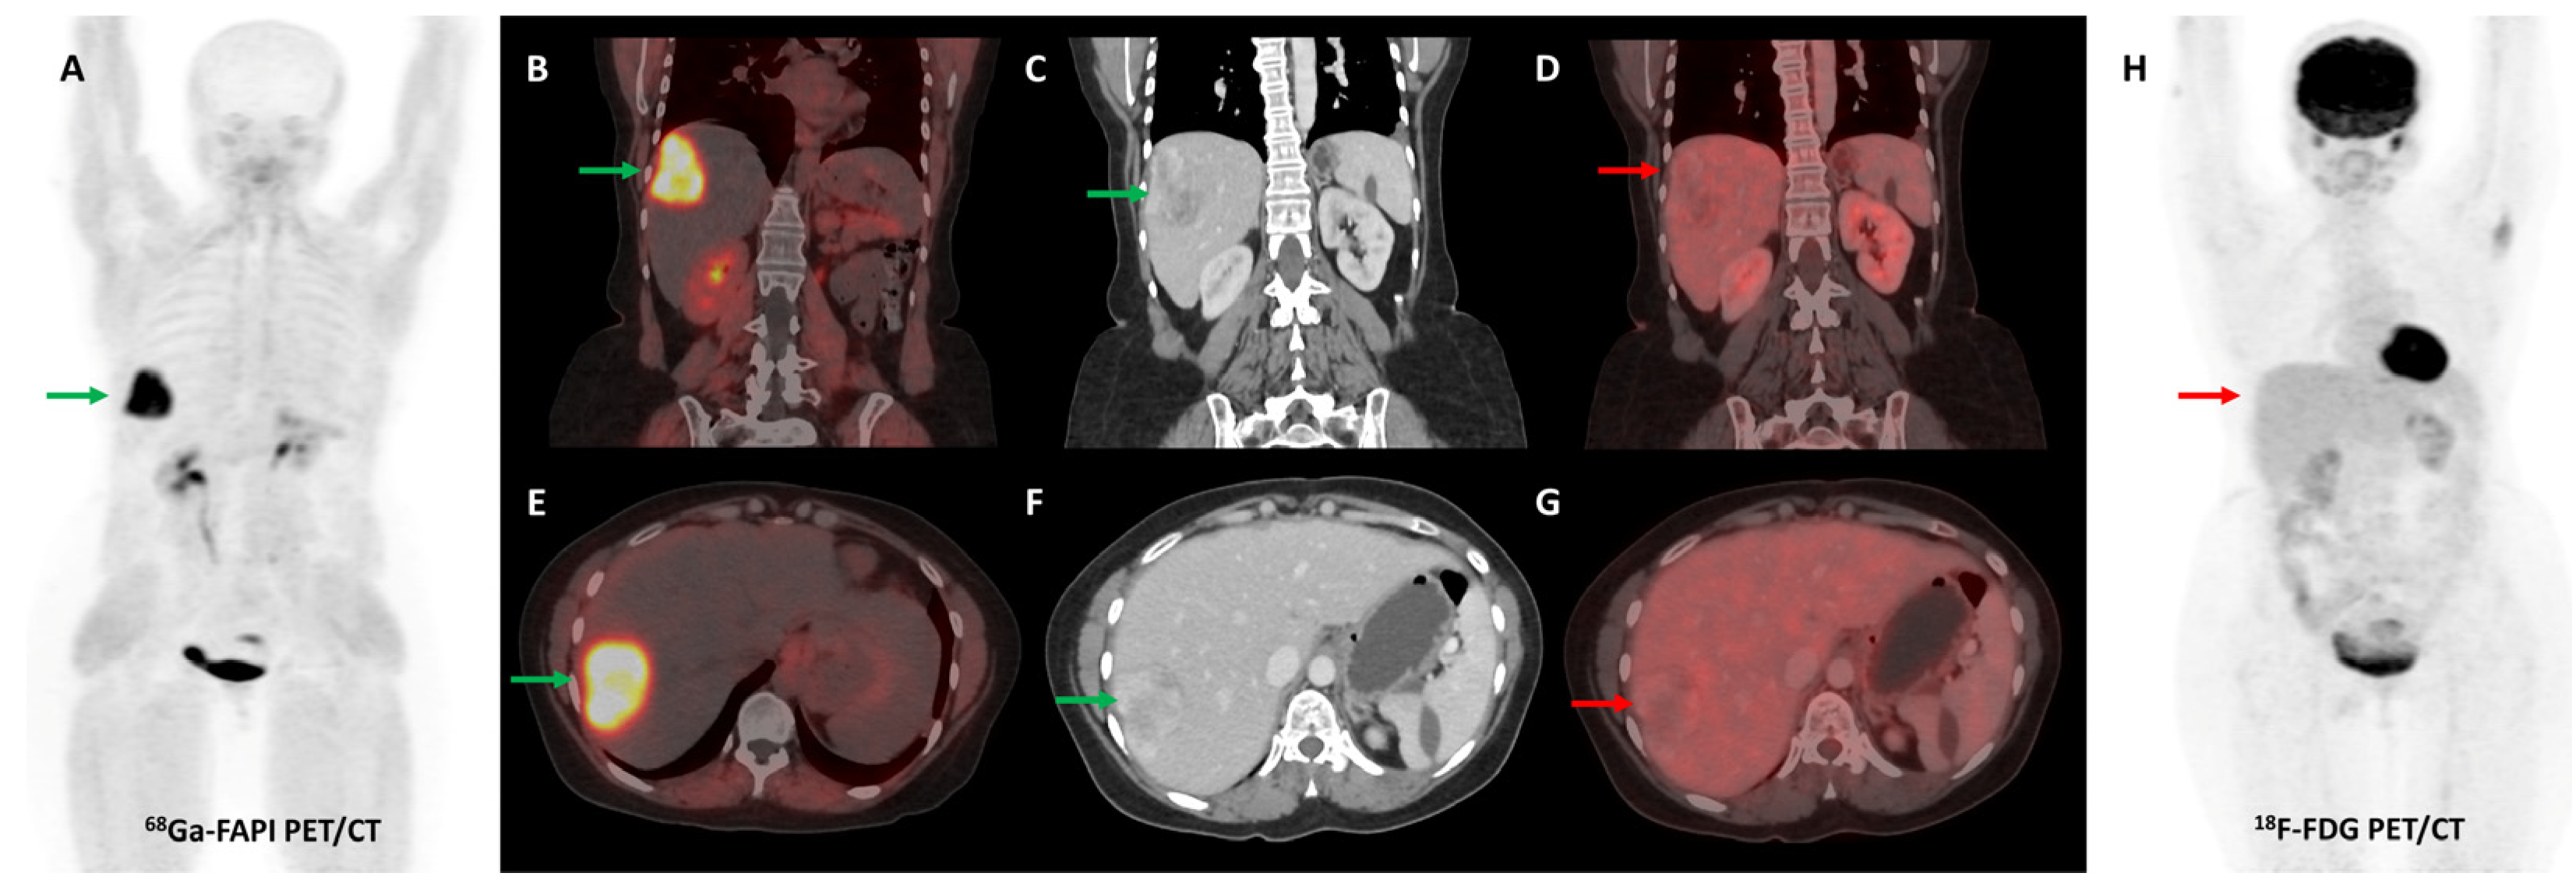

Several preclinical studies have demonstrated FAP expression in a vast majority (>90%) of ovarian cancers with negligible expression in normal ovarian tissue, benign and borderline tumors. FAP expression in epithelial ovarian cancers is associated with resistance to platinum-based chemotherapy, shorter time to recurrence, and overall worse clinical outcomes [113,114,115,116]. In a recent study, [68Ga]Ga-FAPI-04 showed negligible physiological accumulation in ovaries irrespective of the menstrual cycle phase, suggesting that it could overcome limitations associated with non-specific/benign ovarian FDG uptake [117]. Zheng et al. retrospectively compared [68Ga]Ga-FAPI-04 and FDG PET/CT in 21 patients with suspected (n = 11) or already diagnosed (n = 10) primary ovarian malignancy. FAPI was more sensitive than FDG PET/CT for the detection of primary tumors (100% vs. 78%), nodal metastases (100% vs. 80%), and peritoneal/pleural involvement (100% vs. 56%), leading to upstaging of disease in 19% (4/21) of the patients [118]. Figure 8 shows an example of FAPI PET/CT in a patient with ovarian malignancy.

Figure 8.

Forty-seven-year-old woman, a known case of ovarian carcinoma (clear cell type) post-surgery and adjuvant platin-based chemotherapy had rising serum CA-125 levels. She underwent [68Ga]Ga-FAPI-04 and FDG PET/CT for restaging, which revealed a heterogeneously enhancing lesion (~5.1 × 3.5 cm) in segment VII of the liver ((C,F)—green arrows) with intense FAPI uptake ((A,B,E)—green arrows) and no significant FDG uptake ((D,G,H)—red arrows) suggestive of liver metastasis.